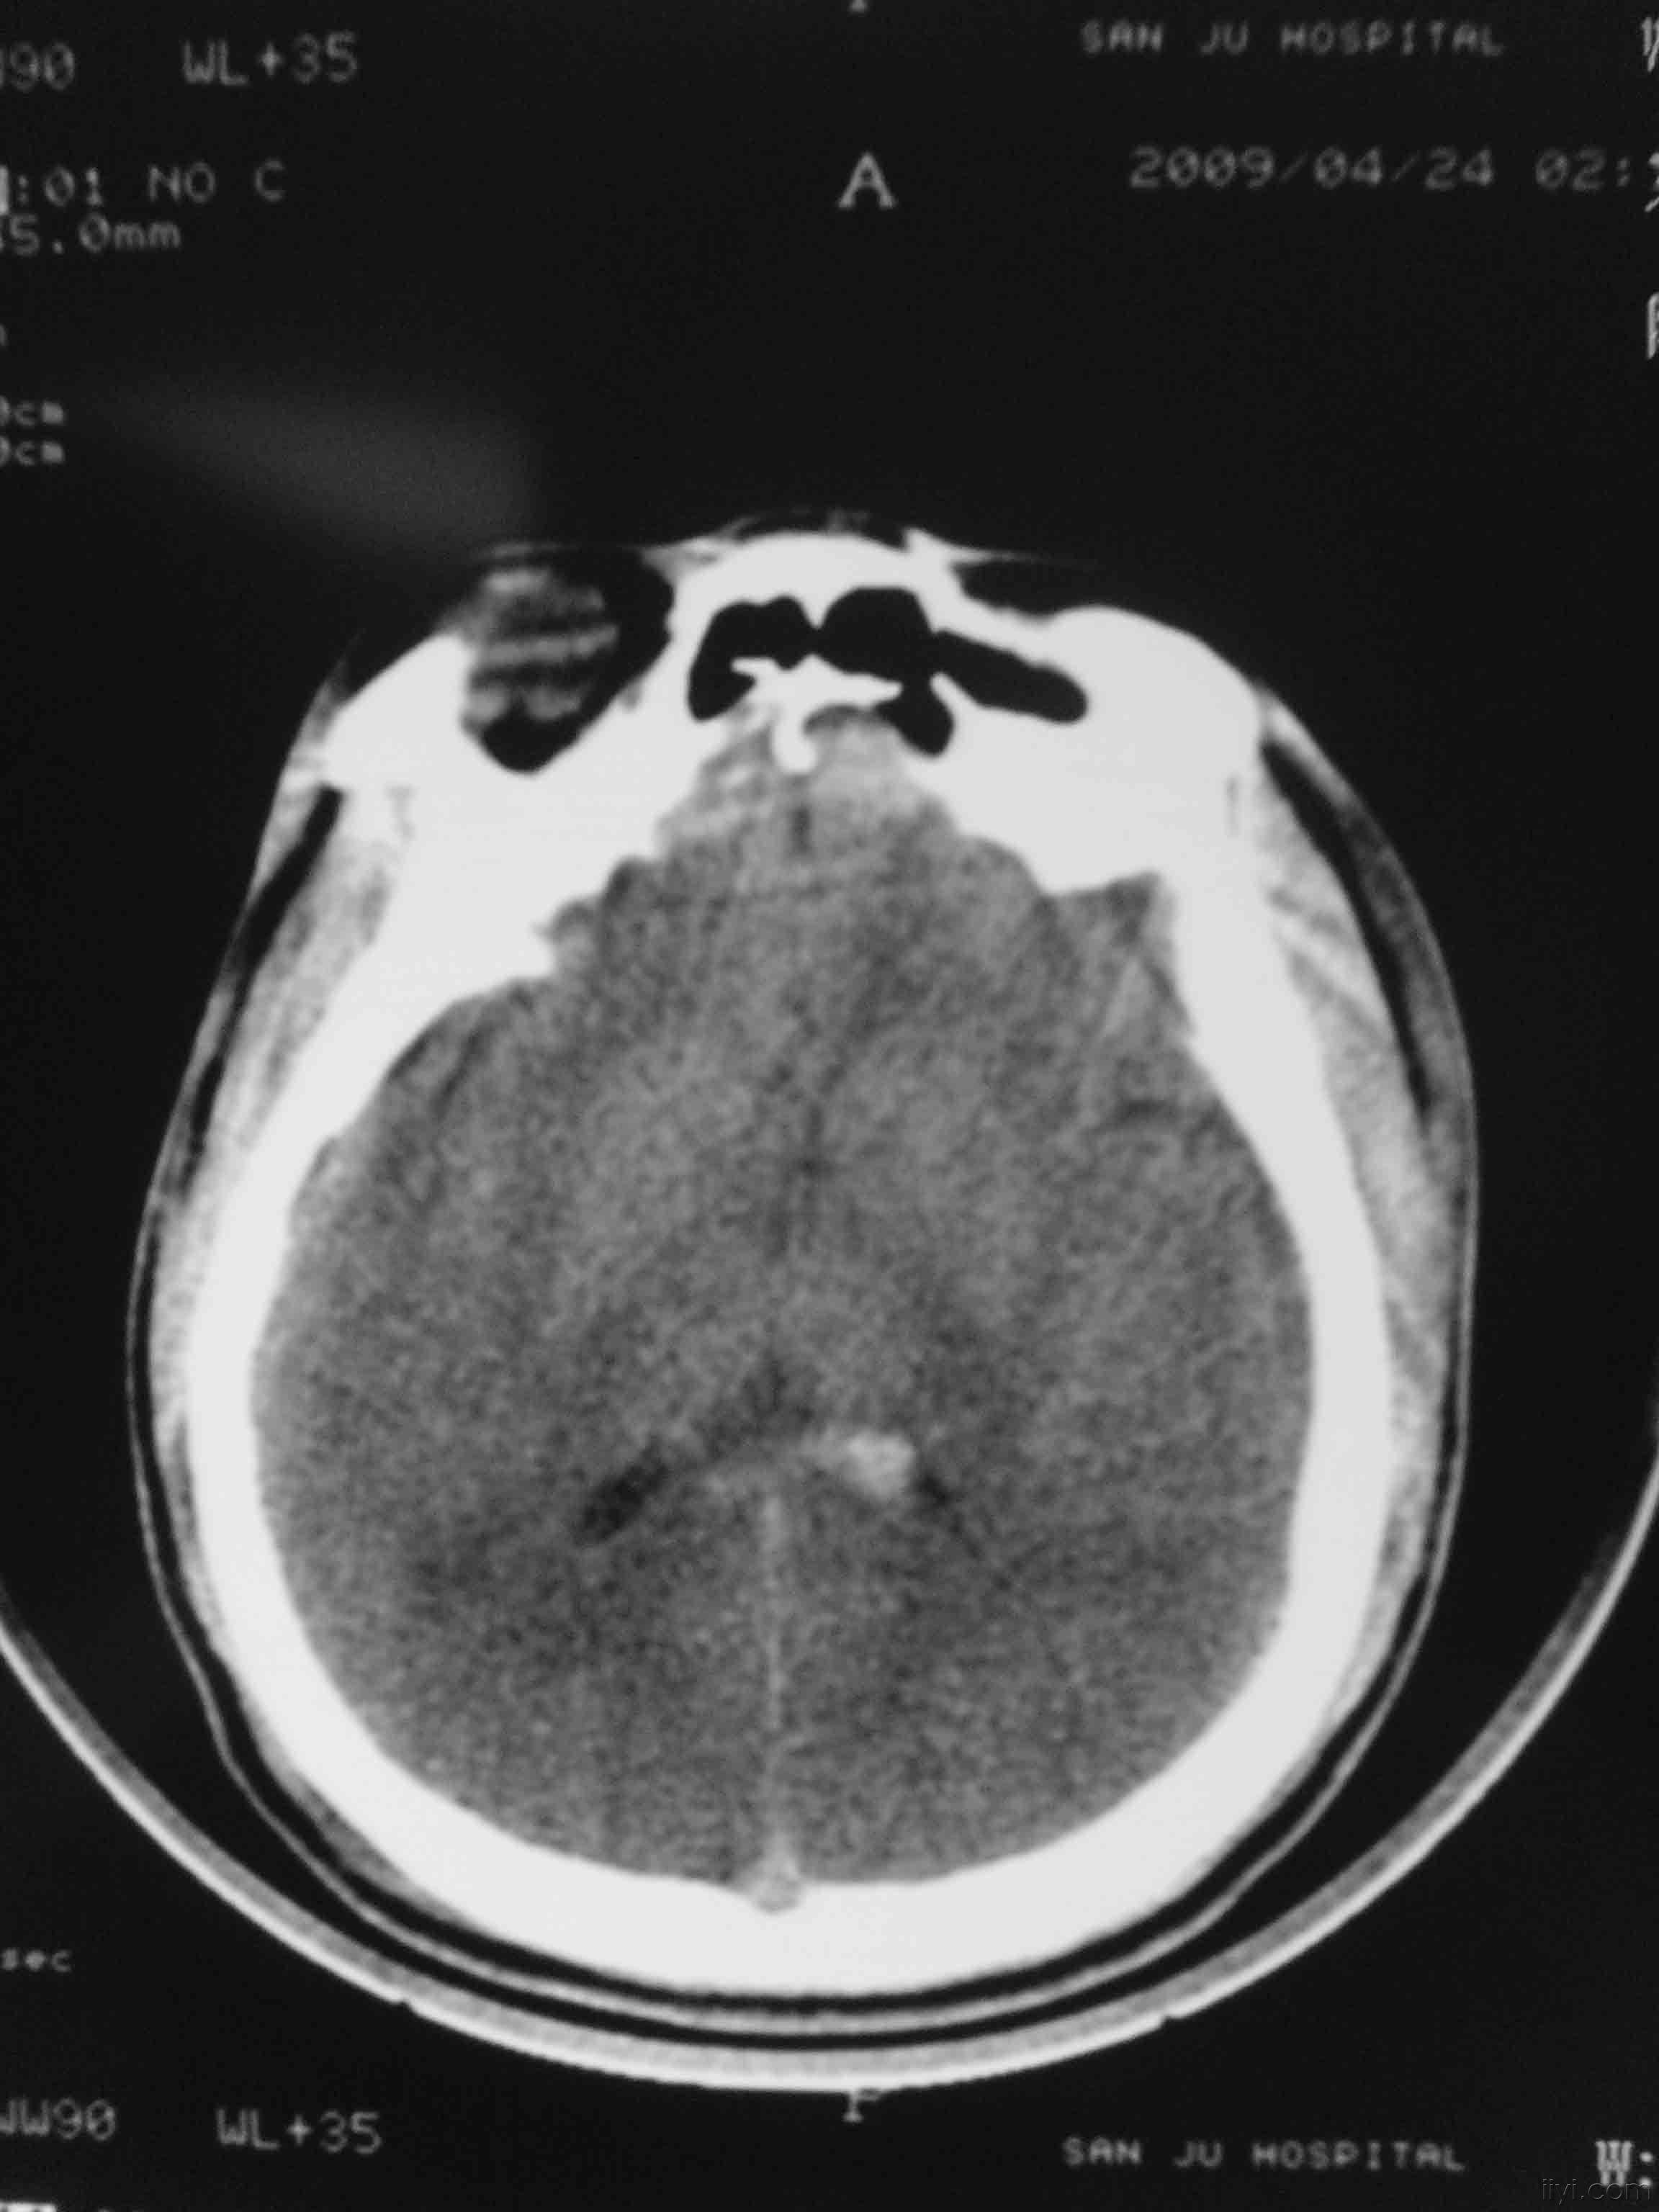

此例颅脑损伤是手术还是保守治疗

图片尺寸2592x1944